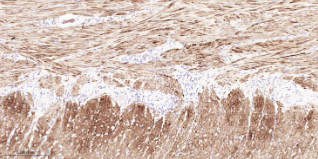

Immunohistochemical analysis of paraffin embedded Human uterus tissue slide using IHC0649H (Human MYL9 Kit).